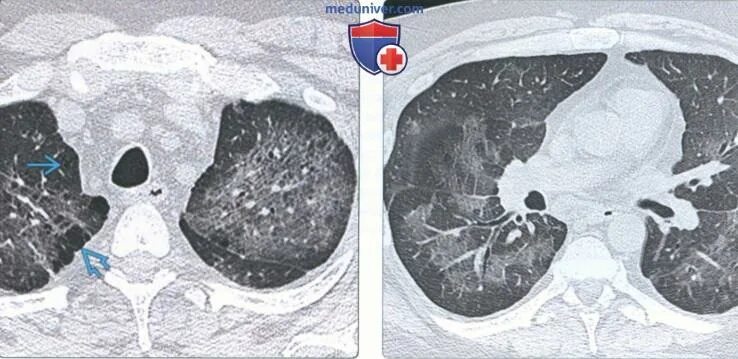

Гипостатические изменения кт